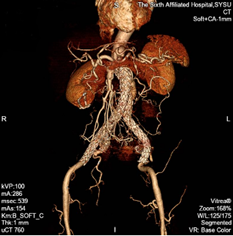

术前CT等影像资料:动脉瘤

术前CTA重建提示:腹主动脉远段、双侧髂总动脉、左侧髂内动脉管腔扩张,左侧髂总动脉瘤最大直径超过42mm。